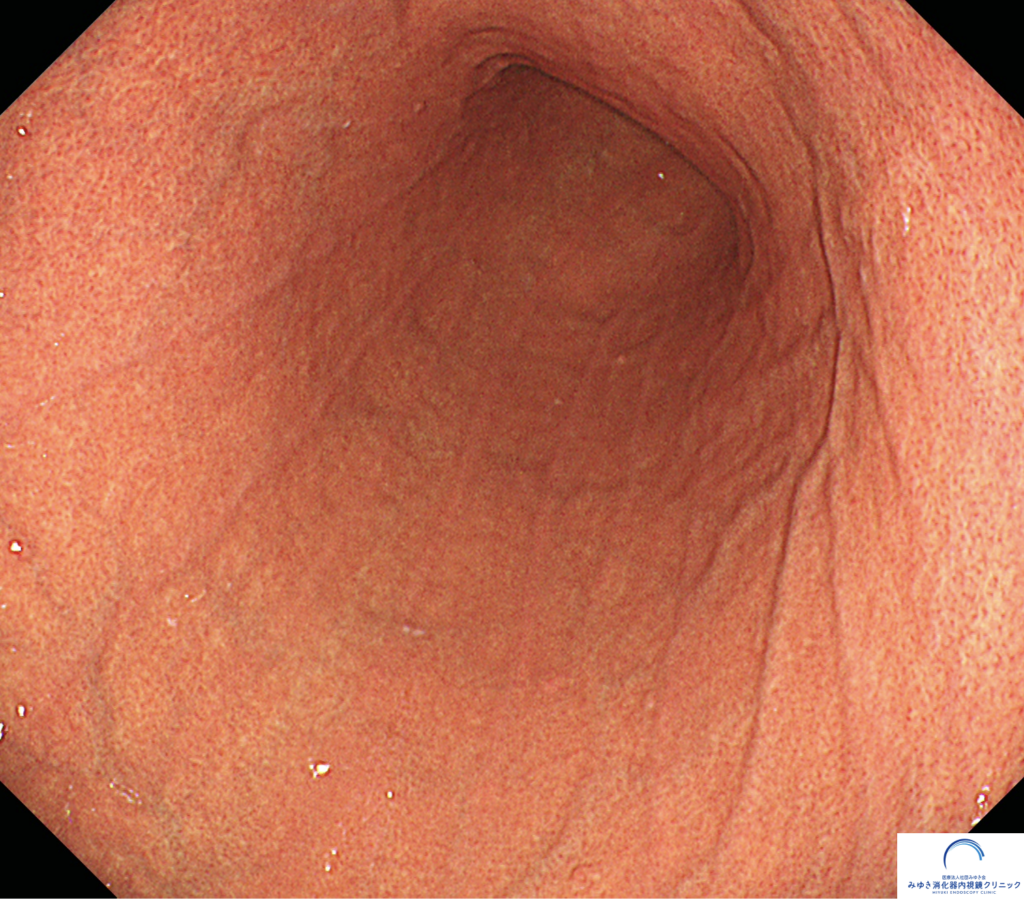

③ 稜線状(りょうせんじょう)発赤

稜線状発赤とは、胃の粘膜に見られる帯状の赤い線で、胃の長軸方向に沿って、数本が平行に並んで見えるのが特徴です。以前は「表層性胃炎」と呼ばれていた所見ですが、発赤が軽度で、ただれ(びらん)や強い炎症を伴っていない場合には、病的な意味はなく正常範囲の所見と考えられています。